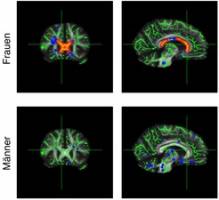

Übergewicht zählt zu den häufigsten Zivilisationskrankheiten und hat eine Vielzahl von negativen Auswirkungen auf die Gesundheit. Dazu gehören auch Veränderungen des Gehirns. Studien der letzten Jahre ergaben, dass Menschen mit stark erhöhtem Gewicht ein geringeres Gehirnvolumen und eine verringerte Gewebedichte in der grauen Substanz haben.